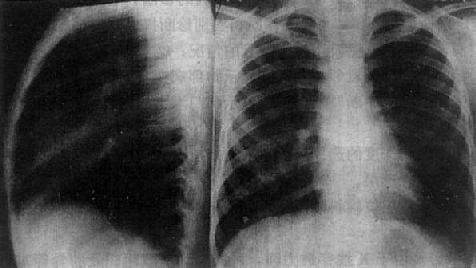

正常胸部X线影像是胸腔内、外各种组织和器官重迭的总合投影。应熟悉生后前位及侧位片上各种影像的正常及变异表现(图3-1-1),以免误诊为病变。

正常胸部侧位、后前位片

图3-1-1 正常胸部侧位、后前位片